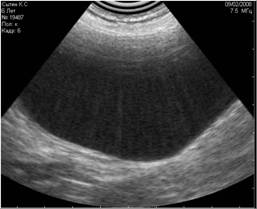

- вызванные движениями животного, в том числе дыхательной экскурсией (Рис.5).

Рис. 5. Помехи, вызванные дыхательными движениями животного. |